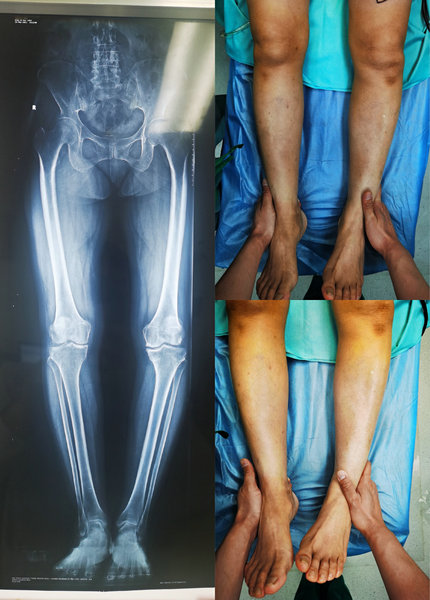

来到骨外科四病区后,刘洋主任对病人进行了查体,发现病人膝关节内翻畸形,伴有一定程度的活动受限,肌肉萎缩,肌肉力量下降,加上病人疼痛症状较明显,上下楼,下蹲,行走等动作,都有不同程度的活动受限。经过一系列系统检查并结合病人的病史、查体及辅助检查可确定诊断为左膝关节骨性关节炎,左膝关节内翻畸形。

术前对比照片